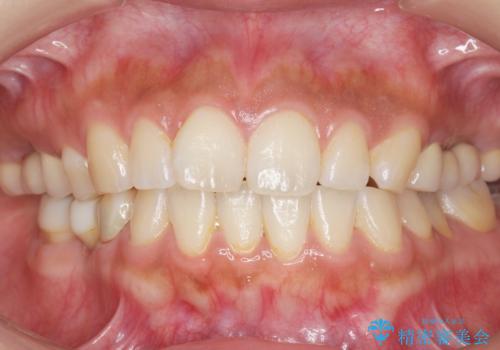

インプラントや入れ歯を使わずに奥歯でしっかり咬むことができるようになり、また見た目も自然だと大変喜んで頂けました。

クラウンの種類:メタルボンドクラウン エコノミー フルベイク